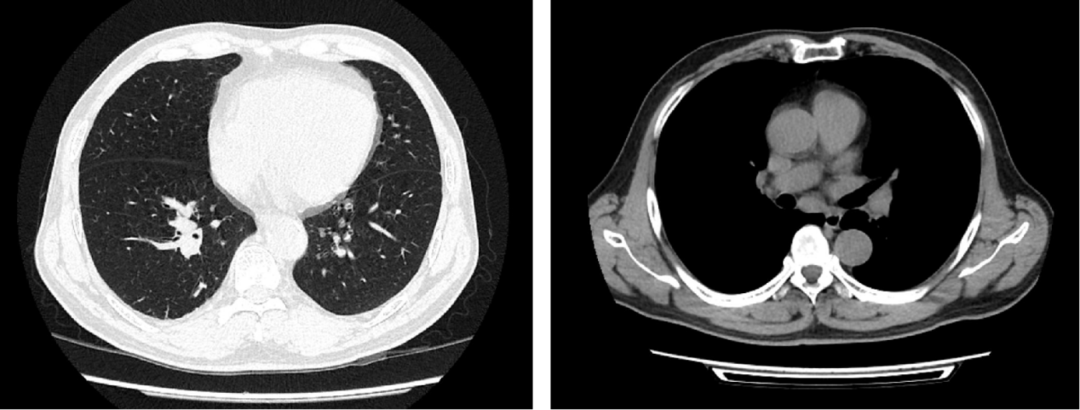

随着免疫治疗的发展,PD-1单抗在包括肺癌、胃癌、食管癌、鼻咽癌等在内的多种实体瘤的治疗中表现出令人鼓舞的治疗潜力,并随着临床证据的积累,发挥着越来越重要的治疗价值。同时,PD-1单抗在局部晚期肺鳞癌患者的新辅助治疗中的价值,也得到临床的积极探索。本期,我们分享一例局晚期肺鳞癌同时合并鼻咽癌的患者接受替雷利珠单抗联合化疗新辅助治疗后,顺利实施肺癌根治术,且鼻咽癌病灶也得到一定缓解的病例。 | 病例提供者:复旦大学附属中山医院厦门医院 王仁峰医生 王仁峰 主治医师 硕士研究生 复旦大学附属中山医院厦门医院 胸外科 中国胸外科三维重建及人工智能联盟常务委员 中国转化医学联盟胸部肿瘤外科专业委员会委员 河北省急救医学会第一届胸外科专业委员会青年委员 河北省健康学会胸外科管理分会第一届委员 河北省呼吸与健康学会微创外科分会委员 一般资料:男性,61岁。 主诉:因“确诊肺恶性肿瘤3月余”入院。 现病史:患者于2020-11-25因咳血就诊厦门市第三医院,查胸部CT示:右肺下叶后基底段见一实性结节,大小约27.6*23.7 mm,纵隔内见多发淋巴结。2020-11-26行支气管镜检查,病理示右下肺低分化鳞癌。 后转诊我院,2020-12-03行PET-CT示:右下肺后基底段代谢增高,符合肺癌并纵隔(7,10R组)多发淋巴结转移;鼻咽部软组织明显增厚,双侧咽旁间隙,右侧颈部区多发肿大淋巴结,鼻咽恶性肿瘤可能。头颅增强MRI结果提示:鼻咽软组织增厚,其余未见明确转移灶。2020-12-04在我院行超声支气管镜(EBUS),术后病理(2020-12-07)示第7组,第10组淋巴结转移性低分化鳞状细胞癌。2021-12-09于我院耳鼻喉科行局麻鼻咽活检术,术后病理(2020-12-15)示:鼻咽部非角化性癌,未分化型;建议先行肺癌新辅助治疗后再行鼻咽部放疗。 既往及个人史:高血压病史8年;口服药物治疗,血压控制可。 影像学检查: 胸部平扫(2020-12-03):右肺下叶见结节状软组织密度影,范围约22×17mm,邻近支气管腔闭塞;右肺中叶及下叶见微小实性结节影(Se5 Im199、217),直径约4-5mm;两肺透亮度稍增强,两肺散在条索影;纵隔内见肿大淋巴结,短径约14mm;胸膜无增厚,胸腔内无积液。影像学诊断:右肺下叶MT机会大,纵隔淋巴结肿大;右肺微小结节,有待随访;轻度肺气肿;两肺少许慢性炎症。见下图: 鼻咽部病理报告(2020-12-10): 鼻咽部组织:灰白灰褐色碎组织,共计直径0.8cm。(鼻咽部组织)送检破碎黏膜组织慢性炎,局部固有膜内见上皮样细胞巢,伴较多炎性渗出坏死物,正在行免疫组化检查以协助诊断。 2020-12-15补充报告:(鼻咽部组织)镜下见少量破碎黏膜组织及较多坏死物,其黏膜固有膜内散在少许上皮样细胞巢,伴细胞异型,免疫组化标记示少许上皮样细胞P63、P40及EBER阳性,部分异型上皮样细胞及上皮标记表达不理想。结合同一病例20AS06823,本例考虑为非角化癌,未分化型。免疫组化(2020-N02641):20AS06945-001: CK7(少量+),p40(部分+),p63(部分+),Ki-67(70%阳性),EGFR(+),CK{pan}(少量+),TTF-1(8G7G)(-);NapsinA(-),EBER(+),CD56(-),CD3(部分淋巴细胞+),Perforin(-),GranB(-),TIA-1(-),CD30(少量+)。 MRI颈部软组织平扫+增强+DWI(2020-12-18): 鼻咽部MRI示鼻咽右侧壁及后壁软组织不规则增厚,咽隐窝消失,增强后可见轻度异常强化,双侧鼻咽旁间隙见肿大淋巴结,较大者位于右侧,最大层面约23 mm×21 mm×35 mm,双侧颈部多发小淋巴结,双侧海绵窦无受侵表现,部分副鼻窦黏膜增厚。 诊断:右下肺恶性肿瘤(鳞癌 cT1cN2M0 ⅢA期)、鼻咽癌、高血压 第一阶段:新辅助免疫联合化疗治疗 治疗方案:患者于2020-12-18至2021-01-09接受“替雷利珠单抗200 mg+紫杉醇(白蛋白结合型)400mg+d1卡铂450mg”2个周期。治疗过程顺利,无严重不良反应。 复查胸部CT(2021-02-01):原2020-12-03片右肺下叶结节,此次未见,纵隔淋巴结稍大,较前片相仿,右肺微小结节,较前相仿,轻度肺气肿;两肺少许慢性炎症。 疗效评价:部分缓解。 继续治疗:患者继续接受“替雷利珠单抗200 mg+紫杉醇(白蛋白结合型)400mg+d1卡铂450mg”治疗至2021-02-23,共治疗4个周期。治疗过程顺利,无严重不良反应。 复查胸部CT(2021-03-16):两肺见小实性结节影(Im34、38、43),直径约4-5 mm;两肺透亮度稍增强,可见小囊样影,两肺散在条索影,增强后未见异常强化灶,纵隔内见稍肿大淋巴结,短径约13mm;胸膜无增厚,胸腔内无积液。影像学诊断:符合右肺MT治疗后改变,两肺小结节,较前片(21-02-01)相仿,轻度肺气肿;两肺少许慢性炎症。提示纵隔淋巴结较前缩小,建议手术治疗。见下图: 第二阶段:手术治疗 患者于2021-04-02,在全麻下行(右侧)经胸腔镜右下肺癌根治术。 术后病理(2021-04-02): (1)右肺下叶切除标本:大小17*8*2.5cm,支切直径1.5cm,距段支切1cm、距表面胸膜0.1cm见一扎线,扎线处见一灰红质稍实区,范围1.5*1.2*1cm,质软,界不清。病理诊断:(新辅助化疗联合免疫治疗后,右肺下叶切除标本)镜下肺组织部分区肺泡腔塌陷伴纤维组织增生及炎症细胞浸润,考虑为炎症性病变。检出支气管旁淋巴结12枚,均呈慢性炎症,其中1枚淋巴结内见组织细胞反应伴坏死及胆固醇结晶形成。 (2)送检分组淋巴结:2.4组淋巴结、7组淋巴结、10组淋巴结、11组淋巴结。病理诊断:送检2.4组淋巴结2枚,均呈慢性炎。送检7组淋巴结9枚,均呈慢性炎,其中2枚淋巴结内见泡沫样组织细胞反应伴胆固醇结晶形成。送检10组淋巴结1枚,呈慢性炎。送检11组淋巴结5枚,均呈慢性炎。 (3)术后病理结果回报(新铺助化疗联合免疫治疗后,右肺下时切除标本)镜下肺组织部分区肺泡腔塌陷伴纤维组织增生及炎症细胞浸润,考虑为炎症性病变(ypTONOMO)。 疗效评估:PCR(病理完全缓解) 第三阶段:肺癌根治术后复查及鼻咽癌处理 肺癌根治术后复查: 胸部CT平扫(2021-5-8):右肺术后,右肺下叶见片絮状磨玻璃密度影,两肺见多枚小结节(im19、29、35、45等),大者直径约4-5mm,所见各支气管腔通畅,肺门及纵膈未见肿大淋巴结,胸膜无增厚,右侧胸腔内见少量积液及积气。右心膈角见稍大淋巴结。影像学诊断:右肺术后,右肺下叶少许炎症,右侧胸腔少量积液、积气,随访;余两肺多发小结节,较前大致相仿,密切随访。右心膈角稍大淋巴结。 鼻咽癌影像学随访: 头部MRI检查(2021-5-11):鼻咽部平扫+增强。结果提示,患者鼻咽右侧壁及后壁软组织稍厚,增强后明显均匀强化,双侧咽旁间隙、胸锁乳突肌深面见多发小及稍肿大淋巴结,较大者约8×8mm,增强后部分呈轻度强化,部分呈明显强化,双侧海绵窦无受侵表现,部分副鼻窦黏膜增厚。影像学诊断:患者为鼻咽癌MT病例:鼻咽右侧壁及后壁稍厚,颈部淋巴结转移,较2020-12-18片病灶及淋巴结均明显缩小,轻度鼻窦炎。疗效评估:PR。 下一步治疗:免疫维持治疗 1. 患者因诊断肺恶性肿瘤入院,经进一步检查后,明确肺鳞癌分期为cT1cN2M0 ⅢA期,同时发现患者存在鼻咽癌病灶。经过多学科讨论后,决定对患者先行肺癌新辅助治疗后再行鼻咽部放疗。 2. 患者先后共接受4个周期的新辅助化疗联合免疫治疗,具体方案为替雷利珠单抗+紫杉醇(白蛋白结合型)+卡铂,治疗过程顺利。影像学复查结果提示,患者纵膈淋巴结较前缩小,可接受手术治疗。 3. 患者如期接受胸腔镜右下肺癌根治术,术后病理提示疗效评估达pCR。术后1月余患者接受胸部影像学复查提示,患者两肺情况较前大致相仿。鼻咽部影像学复查提示,患者鼻咽癌病灶及淋巴结均较之前明显缩小,治疗效果达PR。 范虹 医学博士,复旦大学附属中山医院胸外科主任医师,硕士研究生导师 复旦大学附属中山医院厦门医院大外科主任兼胸外科执行主任 美国哈佛医学院麻省总院research fellow da Vinci Surgical System机器人系统Console Surgeon 上海市医师协会胸外科专业委员会委员、纵隔外科学组副组长 上海市中西医结合学会胸外科专业委员会委员 擅长肺部结节的胸腔镜微创手术及da Vinci机器人系统微创手术;局部晚期肺癌的复杂手术;气管疾病的手术治疗;食管癌的胸腔镜微创手术及da Vinci机器人系统微创手术;胸腺瘤等纵隔肿瘤的胸腔镜微创手术及da Vinci机器人系统微创手术; 以及胸壁肿瘤等其他胸外科疾病的手术治疗 患者为一名右下肺鳞癌同时合并鼻咽癌的患者,肺鳞癌分期为cT1cN2M0 ⅢA期,属于局部晚期;鼻咽癌为鼻咽部非角化性癌伴颈部淋巴结转移。这是一例临床比较少见的同时并发两种癌症的患者,病情复杂。如何为患者制定整体的治疗方案,成为摆在临床医生面前的难题。 2020 CSCO非小细胞肺癌诊疗指南指出[1],对可手术的ⅢA期原发性非小细胞肺癌(NSLCL)患者,推荐给予新辅助治疗。相较于传统治疗,免疫治疗可激活肿瘤特异性T细胞的抗肿瘤作用,与机体自生免疫系统相辅相成,帮助患者获得持久疗效,优势明显。目前已有多项研究初步证实了,免疫治疗具有良好的病理缓解、耐受性、安全性以及无手术延迟等获益潜力,是一种安全有效的NSCLC术前新辅助/辅助治疗手段。近年来PD-1单抗在局晚期肺鳞癌新辅助治疗中的价值得到探索,包括我国自主研发的PD-1单抗替雷利珠单抗。 替雷利珠单抗是一种靶向PD-1的高亲和力、高特异性的人源化IgG4型单克隆抗体,经特殊设计的替雷利珠单抗可最大限度地减少与巨噬细胞表面的Fcγ受体结合,减少巨噬细胞对免疫细胞的消耗,避免了可能存在的免疫治疗耐药问题。与同类单抗相比,替雷利珠单抗在作用机理方面可能具有更多治疗优势。多项临床实际病例也提示,替雷利珠单抗用于肺鳞癌新辅助治疗具有显著治疗获益。 尽管目前尚未有替雷利珠单抗联合化疗用于肺鳞癌新辅助治疗的大规模临床试验出炉,但中国首个、全球第二个成功探索肺鳞癌一线免疫治疗的Ⅲ期研究RATIONALE-307研究显示[2],替雷利珠单抗联合两种化疗方案均能显著降低患者疾病进展风险,延长无进展生存。且无论PD-L1表达如何,替雷利珠单抗联合两种化疗方案患者PFS均获益。这提示,替雷利珠单抗用于肺癌具有显著治疗获益。 同时,该患者还同时是一名鼻咽癌患者,如果单纯对患者进行肺癌新辅助免疫联合化疗,是否会延误鼻咽癌病情?RATIONAL 102研究带来启示。该研究是一项在包括肺癌和鼻咽癌在内的多个实体瘤中探索替雷利珠单抗疗效与安全性的研究[3]。结果提示,替雷利珠单抗单药治疗复发/转移鼻咽癌二线及以上有显著的治疗效果,客观缓解率(ORR)达43%,无进展生存期(PFS)达10.4个月。经过综合考虑,对该患者进行肺癌的替雷利珠单抗联合化疗新辅助治疗,之后再考虑鼻咽癌放疗。结果提示,患者顺利接受肺癌根治术且术后病理达pCR,复查提示鼻咽癌病灶及淋巴结也明显缩小,这表明替雷利珠单抗联合化疗在治疗肺癌的同时,对鼻咽癌也发挥了积极的治疗作用,为后续鼻咽癌的放疗打下了良好的基础。 王鹏 副主任医师、医学博士 复旦大学附属中山医院厦门医院耳鼻喉科执行副主任 美国爱荷华大学医院耳?咽喉头颈外科访问学者 中国研究型医院学会眩晕医学专业委员会委员 中国抗癌协会康复会学术指导委员会头颈?年委员会委员 中国人体健康科促会?科专委会委员 厦门医师协会嗓音分会副会长 擅长耳鼻喉-头颈部良、恶性肿瘤的手术及综合治疗,尤其对喉癌、下咽癌、鼻咽癌的综合诊治有独到见解 该患者为同时伴有局晚期肺部肿瘤和鼻咽癌的患者。影像学检查结果提示,该患者鼻咽软组织增厚,双侧咽旁间隙,右侧颈部区多发肿大淋巴结,其余未见明确转移灶;病理学检查也提示淋巴结转移性低分化鳞状细胞癌。根据2020年CSCO鼻咽癌诊疗指南[4],对于局晚期鼻咽癌患者,优选诱导化疗+同期放化疗,5年生存率可达80%。对于转移性鼻咽癌,则首选系统化疗,且急需新的突破。目前,免疫治疗用于复发转移性鼻咽癌的探索一直在不断深入,且取得了一定成果。例如,相关证据提示,PD-1单抗联合化疗一线治疗复发转移性鼻咽癌,患者病灶较基线得到显著改善[5]。这提示,免疫治疗联合化疗能为鼻咽癌患者带来显著的治疗作用。 RATIONAL 102研究是一项在包括肺癌和鼻咽癌在内的多个实体瘤患者中探索替雷利珠单抗单药治疗二线及以上患者疗效与安全性的研究[3]。结果显示,中位随访9个月时,56例NSCLC患者中,有10例患者部分缓解,21例患者疾病稳定,客观缓解率(ORR)为18%,疾病控制率(DCR)为55%,临床获益率(CBR)为52%。中位随访12个月时,21例鼻咽癌患者中,分别有9例、9例和3例患者达到部分缓解、疾病稳定和疾病进展,ORR、DCR、CBR分别为43%,86%和81%。不论PD-L1表达状态如何,在NSCLC和鼻咽癌患者中均观察到肿瘤缓解。 鼻咽癌是巨噬细胞/T淋巴细胞高度浸润的癌种,病理显示肿瘤微环境与经典霍奇金淋巴瘤(cHL)类似。RATIONALE 203研究是一项评价替雷利珠单抗治疗复发/转移cHL的Ⅱ期研究[6],结果提示,替雷利珠单抗单药治疗复发/转移cHL的CR高达62.9%。有理由推测,替雷利珠单抗用于鼻咽癌也将可能取得显著治疗效果。以上证据提示,替雷利珠单抗对于同时患有肺癌和鼻咽癌的患者,可能具有“一举双得”的治疗效果。 本病例中患者同时患有局晚期肺癌与鼻咽癌,在其接受替雷利珠单抗联合化疗的肺癌新辅助治疗后,患者肺癌病灶显著缩小,顺利接受根治术并达到pCR。而鼻咽癌通过影像学评估后也得到一定缓解,提示这种“一举双得”的治疗效果是真实存在的。这为未来免疫治疗药物在鼻咽癌领域的探索提供了一定的启示,并在选择获益人群、制定更有效免疫联合治疗方案方面,引发了更多有意义的思考。基本情况